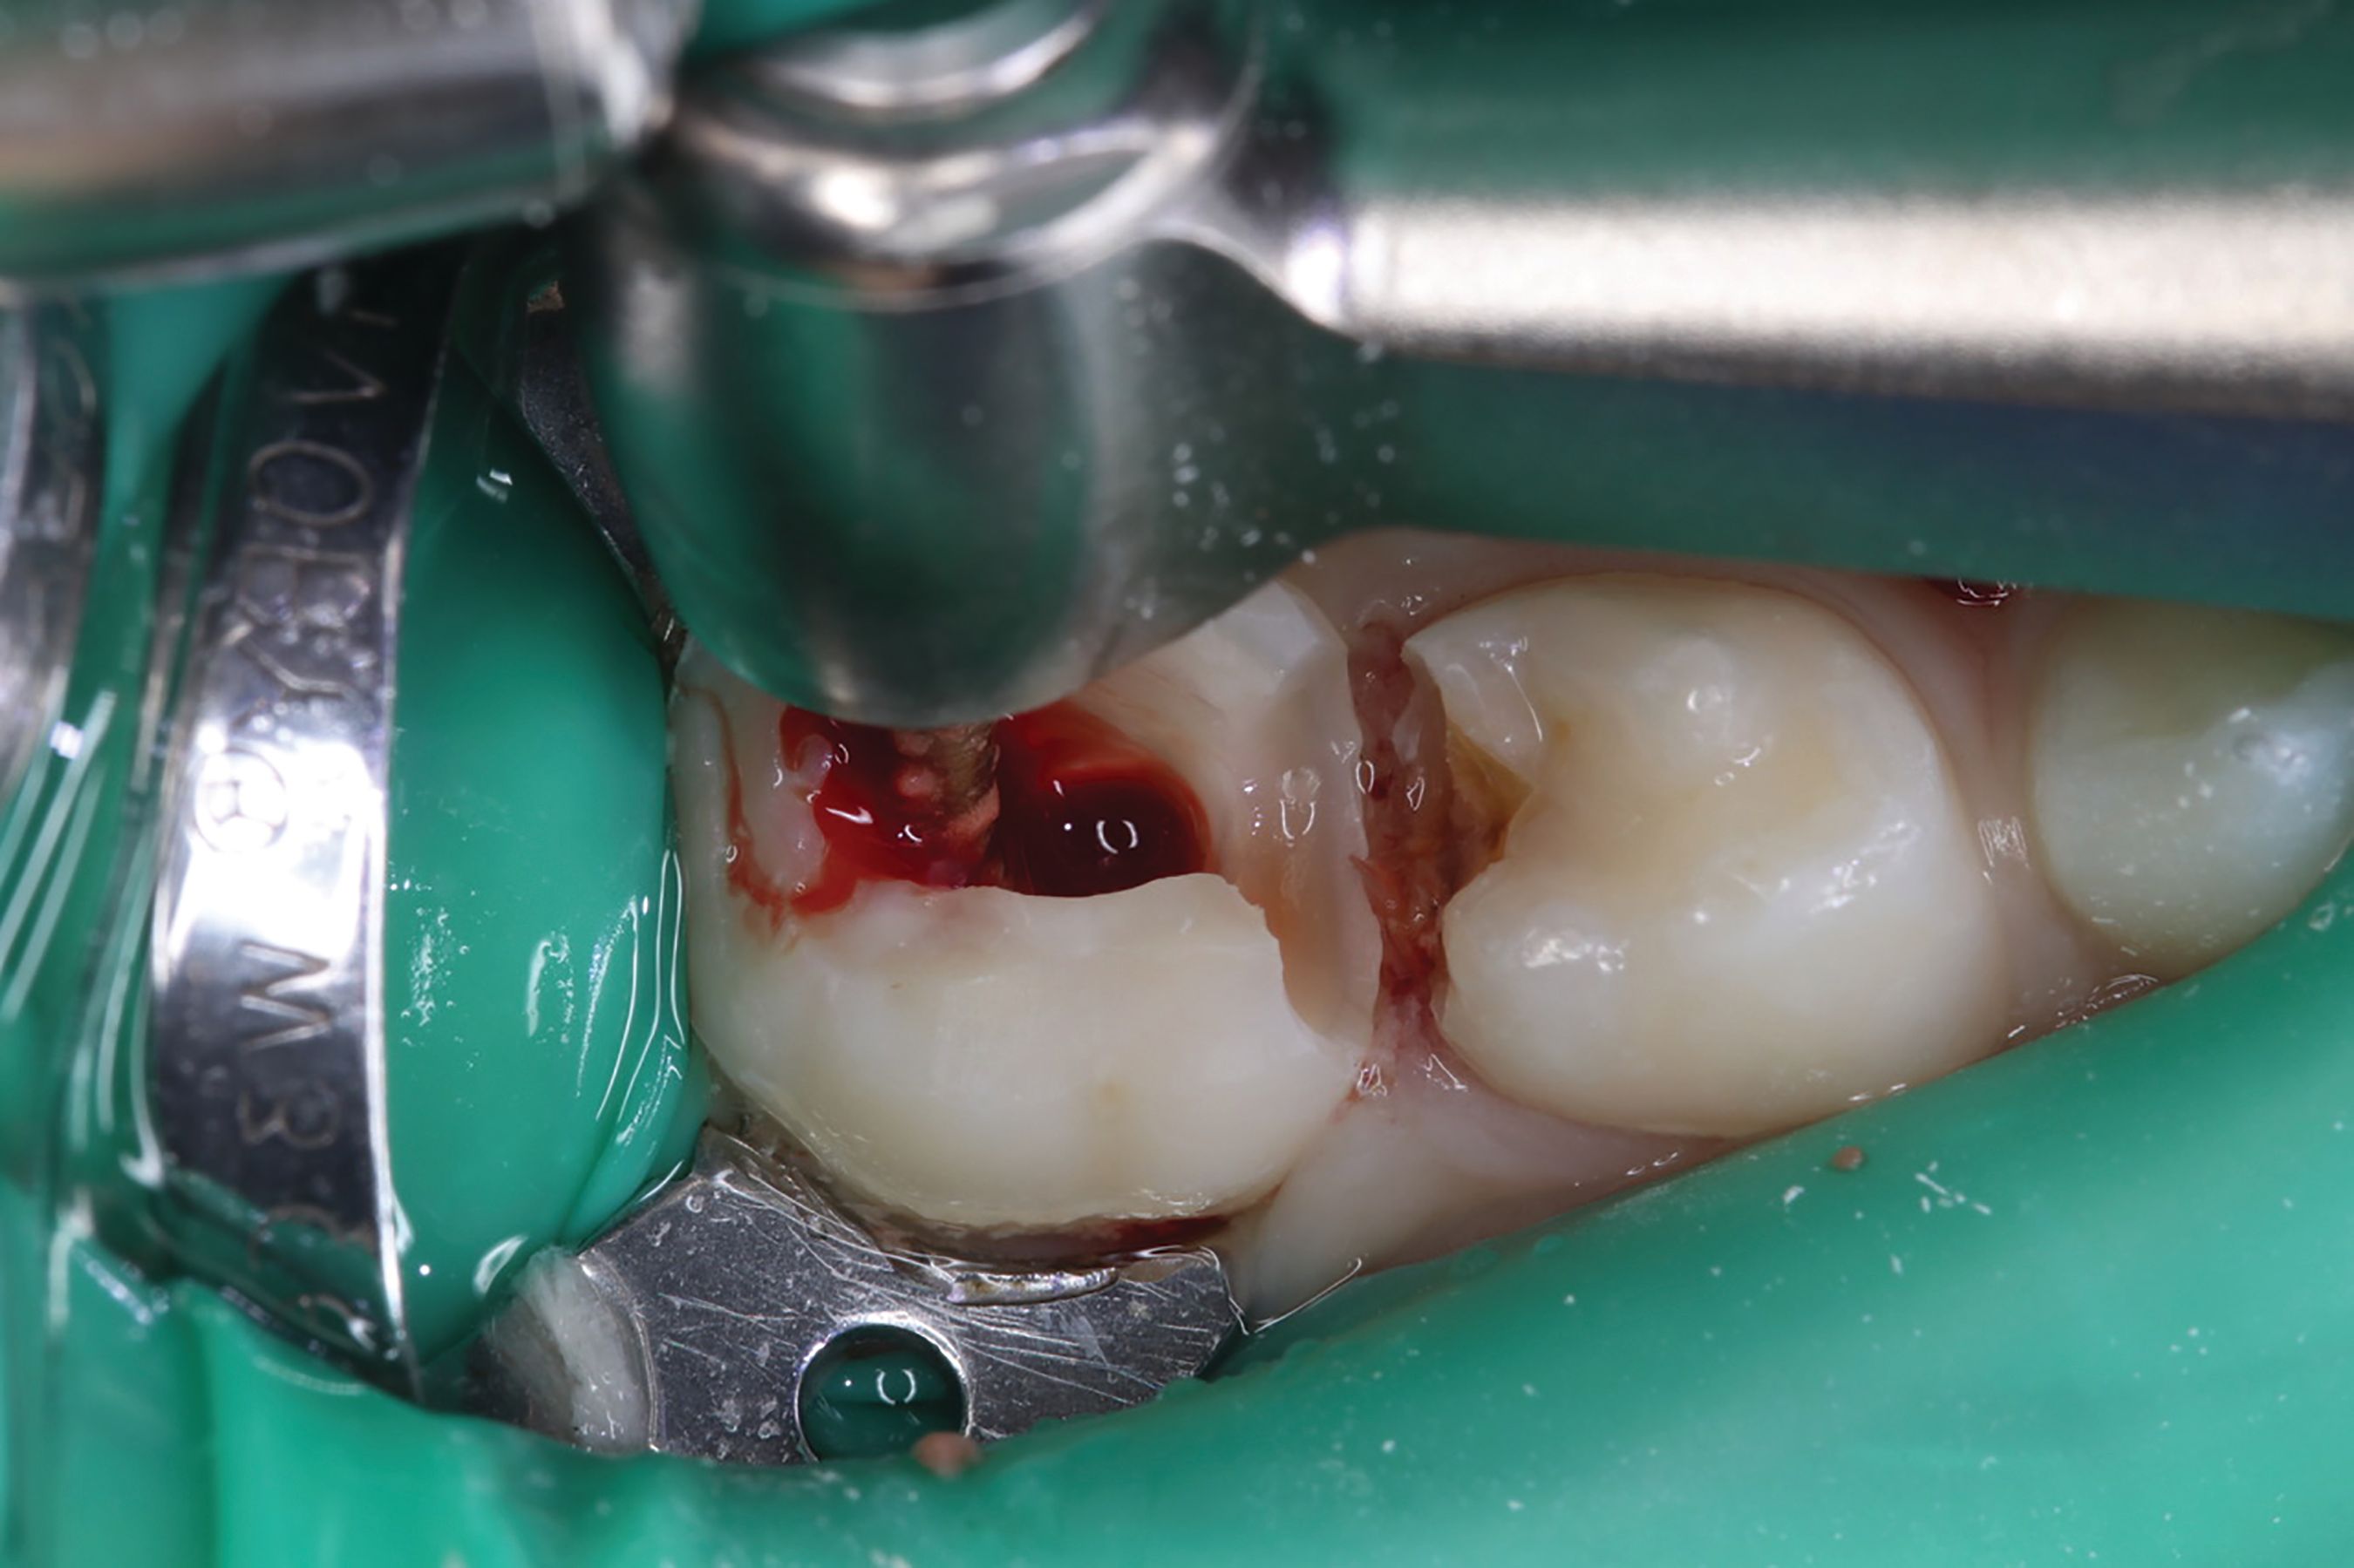

AT A GLANCE [ Figs. 1-9 ] Pre-operative view-primary second molar requiring pulpotomy procedure (Fig. 1). Amputation of coronal pulp chamber to level of radicular pulp stumps with NSK Dental’s slow speed large round bur #8, removing coronal pulp tissue with gentle upward motion (Fig. 2). Hemostasis achieved with saline-soaked sterile cotton pellet (Figs. 3 & 4). Hemostasis achieved (Fig. 5). Extrusion of TheraCal PT into pulp chamber, being sure to reach base of coronal pulp chamber with material and without voids or bubbles and light cure (Figs. 6 & 7). Cured TheraCal PT (Fig. 8). Full-coverage stainless-steel crown (Fig. 9).

Pre-operative view shown in Figure 1. Primary second molar requiring pulpotomy procedure.

Amputation of coronal pulp chamber to the level of radicular pulp stumps was performed with NSK Dental slow speed large round bur #8, removing coronal pulp tissue with gentle upward motion (Fig. 2). Hemostasis is achieved with a saline-soaked sterile cotton pellet (Figs. 3-4). Figure 5 also illustrates hemostasis.